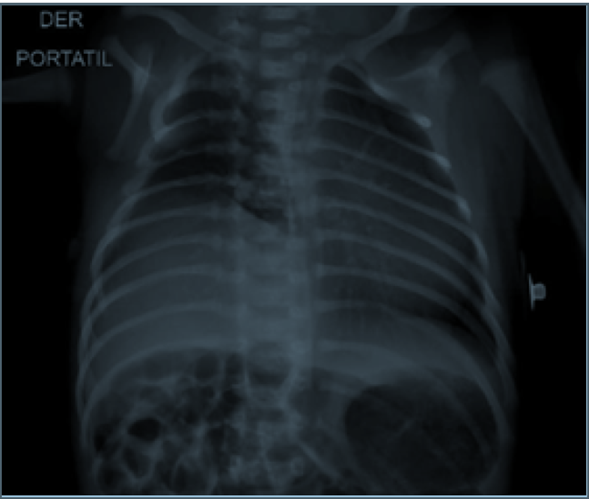

Neonato a término, masculino, parto por cesárea, con adaptación neonatal espontánea, Apgar 7-9, logrando metas de saturación, se encontró asimetría en la expansión del hemitórax derecho, un apéndice que protruye del tórax, pezón descendido y ausencia de continuidad de arcos costales quinto y sexto, sin requerimientos de oxígeno ni signos de dificultad respiratoria, se traslada a unidad de cuidados intensivos neonatales para estudios complementarios, inicialmente radiografía de tórax (Figura 1).

Figura 1 Radiografía de tórax: elevación del hemidia fragma derecho. No hay alteración del parénquima pul monar. Disminución del volumen pulmonar derecho.

Se realizaron estudios ecográficos de cerebro, corazón, vías urinarias y abdominal dentro de límites de normalidad, cirujano pediátrico describe: tórax con asimetría, atrofia del hemitórax derecho, no se palpan algunos cuerpos costales y presenta una masa blanda en la piel de pedículo estrecho que se extrae fácilmente (Figura 2), sin evidencia de alteraciones a nivel de manos, con impresión, diagnostica: sospecha de síndrome de Poland, sin indicación quirúrgica, ecografía de tórax y pleura con movilidad diafragmática normal, sin signos de engrosamiento pleural, sin derrame pleural. En TAC de tórax se describe: elevación del hemidiafragma derecho con disminución del volumen del pulmón derecho, además, acortamiento de los arcos costales derechos del primero al sexto.

Se describe una clasificación de tres tipos refiriendo las anormalidades más frecuentes que acompañan el defecto en el músculo pectoral. Tipo 1 o mínimo: defecto pectoral aislado; tipo 2 o parciales: defecto músculo pectoral con A: anomalía de las extremidades, o B: con anormalidad de las costillas, y tipo 3 o completa: defecto pectoral asociado de alteración de los miembros superiores y las costillas9. El paciente descrito en caso clínico se puede clasificar en tipo 2B por la presencia de alteraciones a nivel del hemitórax derecho, con asimetría torácica evidente clínica y radiológicamente, la afectación por acortamiento de arcos costales 1, 2, 3, 4, 5 y 6, areola hipoplásica, sin afectación de extremidades, se descartó compromiso cardíaco, urinario y hepatobiliar. Sin indicación de tratamiento quirúrgico para corregir deformidad torácica, pero con necesidad de seguimiento durante la infancia y la pubertad1,3.